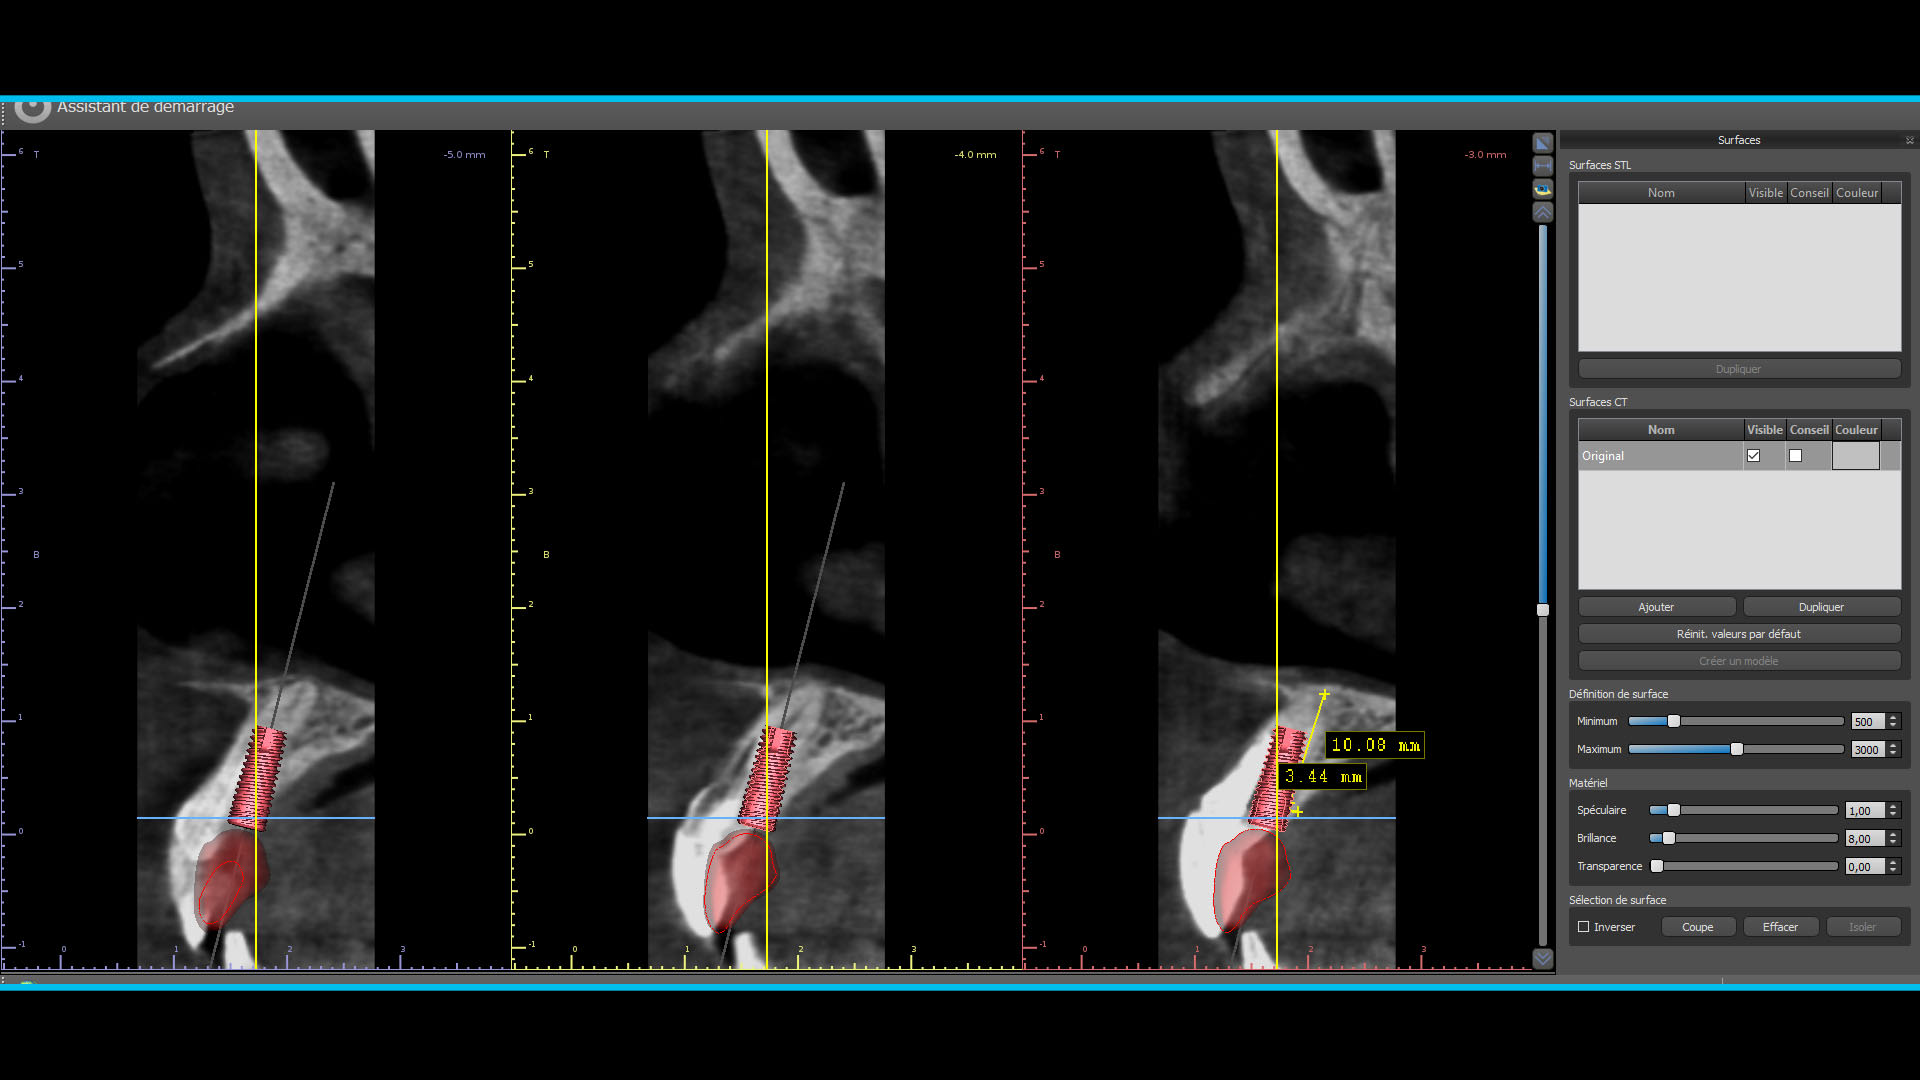

Quelques images du cone beam et de la planif

Planif 1 owxhvi - Eugenol

Planif 2 slmeas - Eugenol

Planif 3 v71j9j - Eugenol

Planif 4 my2dza - Eugenol

Planif 5 fqtf2p - Eugenol

Planif 6 ody3rj - Eugenol